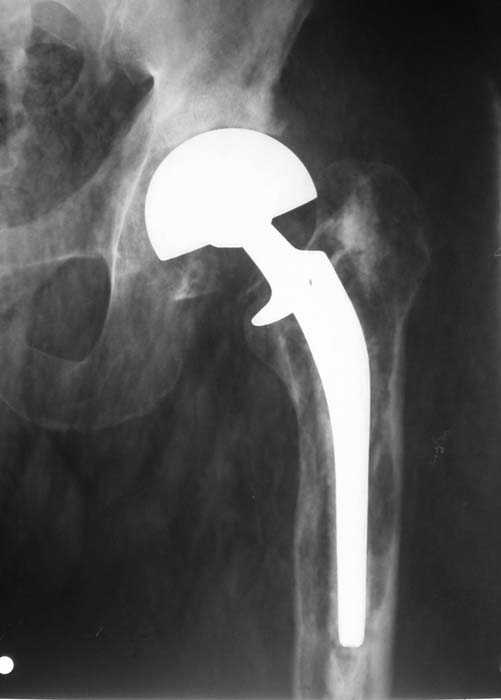

Мужчина, 39 лет.По поводу двустороннего асептического некроза головок бедренных костей последовательно выполнено тотальное эндопроезирование левого (1998 г), затем правого (1999 г) тазобедренных суставов.

26/06/06

Нет никакого смысла делать операцию в два этапа. С чашкой все понятно - стандартный подход с установкой пресс-фит компонента. На бедре имеет

место перипротезный перелом В3 типа - т.е. перелом вокруг ножки с ее нестабильностью на фоне выраженного остеолиза. Решение - доступ к каналу

через перелом с удалением самой ножки, костного цемента и рубцовых тканей. Установка ножки дистальной фиксации (типа Solution), длину ножки

надо определить по шаблону. Минимальный контакт ножки с интактной костью - 6-8 см. Фрагменты проксмального отдела собираются на ножке

эндопротеза, дефекты костной ткани заполняются чипсами (аллографт) и фиксируются кортикальными аллографтами, уложенными дополнительно по типу

"вязанки хвороста" серкляжом. Мы имеем 8 или 10 подобных наблюдений и результатами довольны.